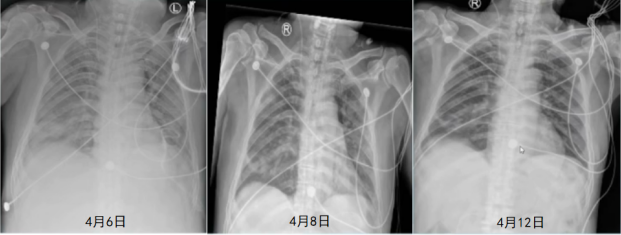

胸部CT:双肺多发片絮状,考虑感染;右肺上叶前段及左肺下叶多发结节(图1)

图1  患者胸部CT